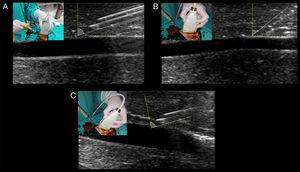

Ultrasound-guided vascular cannulation: the procedure itselfStatic vs real-time techniquesOnce a target vessel is selected, cannulation can be executed using an static technique (US-guided vascular location and skin marking but without using real-time US guidance) (Video 1) or using a dynamic or real-time technique, consisting in observing the screen for direct or indirect signs of the needle entering into the vessel.2,7 (Videos 2, 3 and 4). Both US techniques are more successful for cannulation in comparison with the landmark technique.2,7 When comparing the static and dynamic techniques, the latter has demonstrated a better performance for vascular cannulation compared to the former.2,7 Advantages of the static technique is that it does not require sterile covers for the probe or a needle-screen coordination by the operators. On the other hand, in the real-time technique, cable and probe protection (as well as using sterile US gel) is needed to maintain a sterile technique, the latter usually resulting in some loss of resolution. Additionally, dynamic techniques require a perfect coordination between needle insertion, screen observation and the evaluation of blood returning from the needle, skills that necessarily require proper training and learning curve.

Real-time techniquesFor US-guided real-time vascular cannulation, there are two main ways to reach the vessel: short axis and long axis1,2,7 (Video 2 and 3). There is a hybrid approach between the two techniques mentioned above called the “oblique” technique1,10 (Video 4).

In short axis cannulation, the vessel is centered on the screen and the needle is inserted in the middle, as close to the transducer as possible, and is advanced intersecting the ultrasound beam as shallow as possible to enhance needle visualization (see below). Since the tip of the needle commonly exceeds the body of the transducer as is inserted, observing the needle tip is difficult; in fact, the body of the needle (or its derived reverberation artifacts) is the portion seen7,11 (Fig. 5A). This explains why this technique is usually considered an “out of plane” technique. When using this approach, indirect signs of cannulation are important, such as the movement of the superficial tissues and the flattening of the anterior vessel wall as the needle is advanced into the vessel.

Real-time US-guided vascular cannulation. (A) Short axis (out of plane) technique. Arrows: needle and its reverberation artifact; (B) long axis (in plane) technique. Arrows: needle body, Arrowhead: needle bevel; (C) oblique (in plane) technique. Arrows: needle body; arrowhead: needle bevel.

In the long axis technique, the needle follows the path of the transducer and the ultrasound beam; therefore, it is completely visualized, including the bevel, advancing from the superficial tissues (using the ski lift technique and a shallow insertion angle, see below) up to its definite position into the vessel7,8,11,12 (Fig. 5B). This is why this technique is commonly considered an “in plane” technique. Using the probe orientation mentioned above, the needle is observed as is advanced from the right side of the screen; however, individual practitioners may prefer to see the needle from the other side (this can be achieved by changing the probe orientation or simply inverting the indicator probe positioning in the screen without changing the probe orientation).

Using the oblique technique, the needle is usually advanced using an “in plane” approach10 (Fig. 5C).